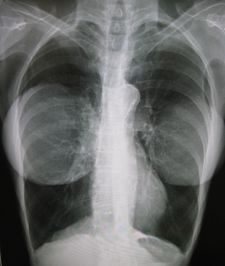

تكبير الثدي

قبل إجراء تكبير الثدي (يسار)، وبعد إجراء تكبير الثدي (يمين). | |